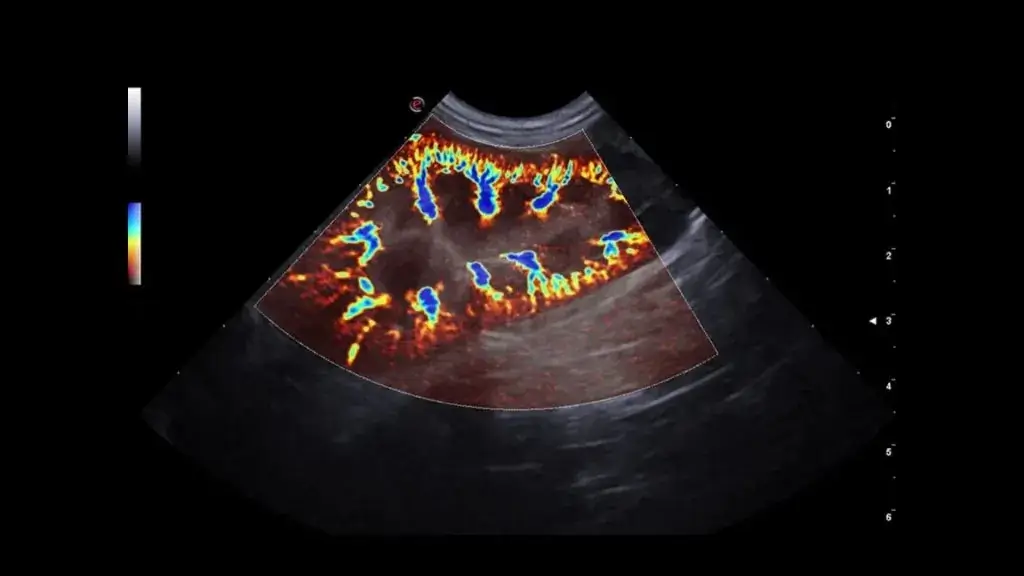

• Gerekli görülen durumlarda Doppler USG ile kan akımı analizi yapılabilir.

Gerekli durumlarda Doppler ile direnç indeksi gibi parametreler incelenebilir.

Gerekli durumlarda Doppler ile vasküler yapıların analizi yapılabilir; portosistemik şant şüphesinde yönlendirici olabilir.

Teknik Altyapımız

Merkezimizde, veteriner kullanımı için üst düzey teknik özelliklere sahip renkli Doppler ultrasonografi sistemi ile hizmet verilmektedir. Cihaz altyapımız; gerçek zamanlı görüntüleme, Doppler kan akımı analizi ve yüksek çözünürlüklü değerlendirme imkânı sunarak birçok patolojinin tanısında hekimlerimize güçlü bir klinik destek sağlar.